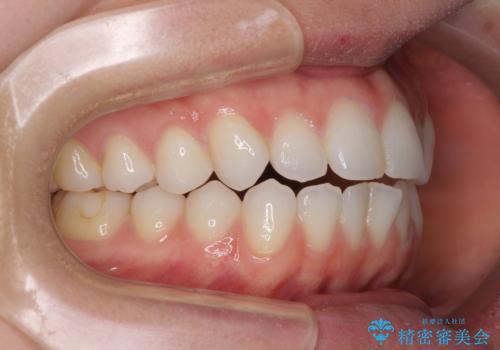

上下前歯が接触しない オープンバイトをインビザラインで改善

- 前歯の上下スペースによる食べにくさを気にして来院された患者様です。

インビザラインにより上下の前歯の隙間を閉じていくこととしました。

上下の奥歯を圧下させるようにすることで、前歯を接触させるように計画しました。

上下の隙間に舌が入り込むことがオープンバイトの原因であったため、舌の筋肉のトレーニングも並行して行い、後戻りの抑制を図りました。